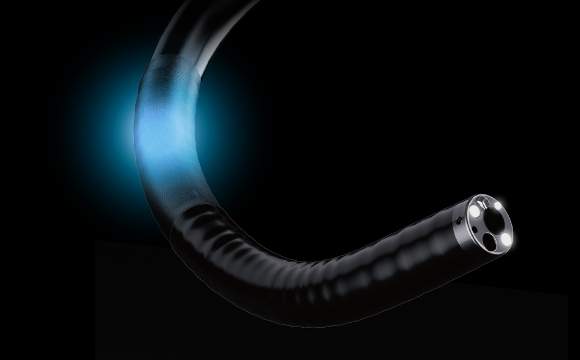

Обзор на 170°Новый колоноскоп серии 50 имеет область обзора 170°, что расширяет диапазон обследования, уменьшает количество слепых зон и, тем самым, снижает частоту ошибочной диагностики кишечных заболеваний. 3 СветоводаИнновационная система подсветки тремя светододами на дистальном конце обеспечивает более масштабное и равномерное освещение во время проводения процедур. В сочетании с широким полем обзора это обеспечивает высочайшее качество изображения.

3 СветоводаИнновационная система подсветки тремя светододами на дистальном конце обеспечивает более масштабное и равномерное освещение во время проводения процедур. В сочетании с широким полем обзора это обеспечивает высочайшее качество изображения. Функция струи водыОснащен функцией прямой дополнительной струи воды, которая позволяет в любое время промыть слизистую оболочку пищеварительного тракта и область рассечения, для сохранения операционного поля чистым и быстрого выявления мест кровотечения.

Подсветка с тремя световодами. На дистальном конце эндоскопа расположены три мощных светодиодных источника, равномерно распределяющие свет по всему полю зрения. Такая конфигурация:

- уменьшает тени и засветки,

- обеспечивает стабильную яркость даже при поворотах эндоскопа,

- улучшает визуализацию слизистой оболочки, особенно при использовании хромоэндоскопии.